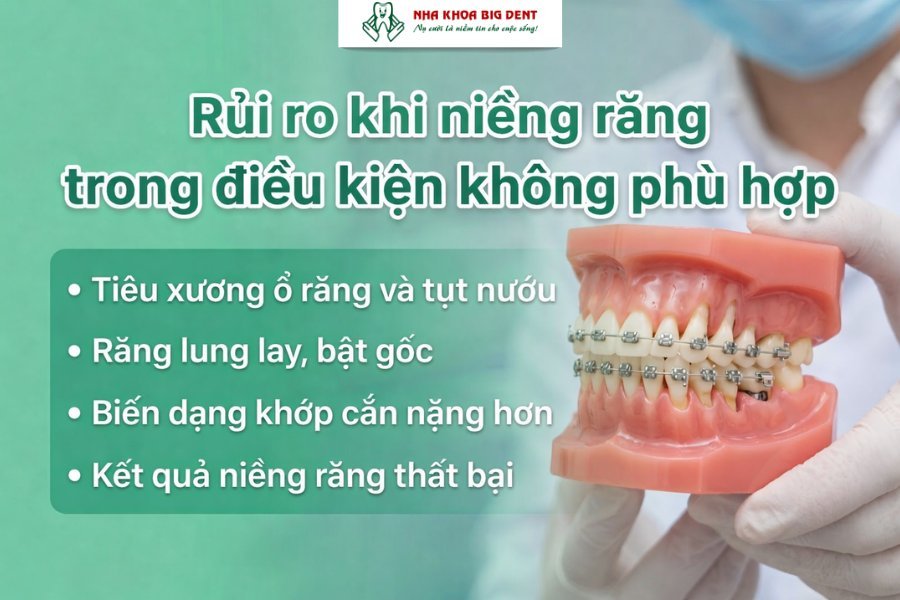

Những rủi ro nếu niềng răng khi chưa đủ điều kiện

Nếu niềng răng khi chưa đủ điều kiện, bạn có thể gặp phải nhiều biến chứng và rủi ro không mong muốn như:

- Tiêu xương ổ răng và tụt nướu: Lực kéo từ khí cụ khiến vùng xương bị áp lực quá tải. Nếu bạn đang bị viêm nha chu, xương hàm sẽ tiêu biến nhanh, làm lộ chân răng và gây ê buốt kéo dài.

- Răng lung lay, bật gốc: Khi mật độ xương không đủ, răng mất đi điểm bám vững chắc. Kết quả là răng bị di động quá mức, thậm chí rơi rụng vĩnh viễn do không thể chịu nổi lực chỉnh nha.

- Biến dạng khớp cắn nặng hơn: Việc ép răng di chuyển trên một nền tảng không ổn định thường dẫn đến sai lệch trục. Điều này gây ra hội chứng loạn năng khớp thái dương hàm, dẫn đến đau đầu và khó khăn khi ăn nhai.

- Kết quả niềng răng thất bại: Toàn bộ quá trình chỉnh nha có thể không đạt mục tiêu ban đầu. Người bệnh vừa tốn thời gian, vừa tăng chi phí và có thể phải điều trị lại từ đầu.